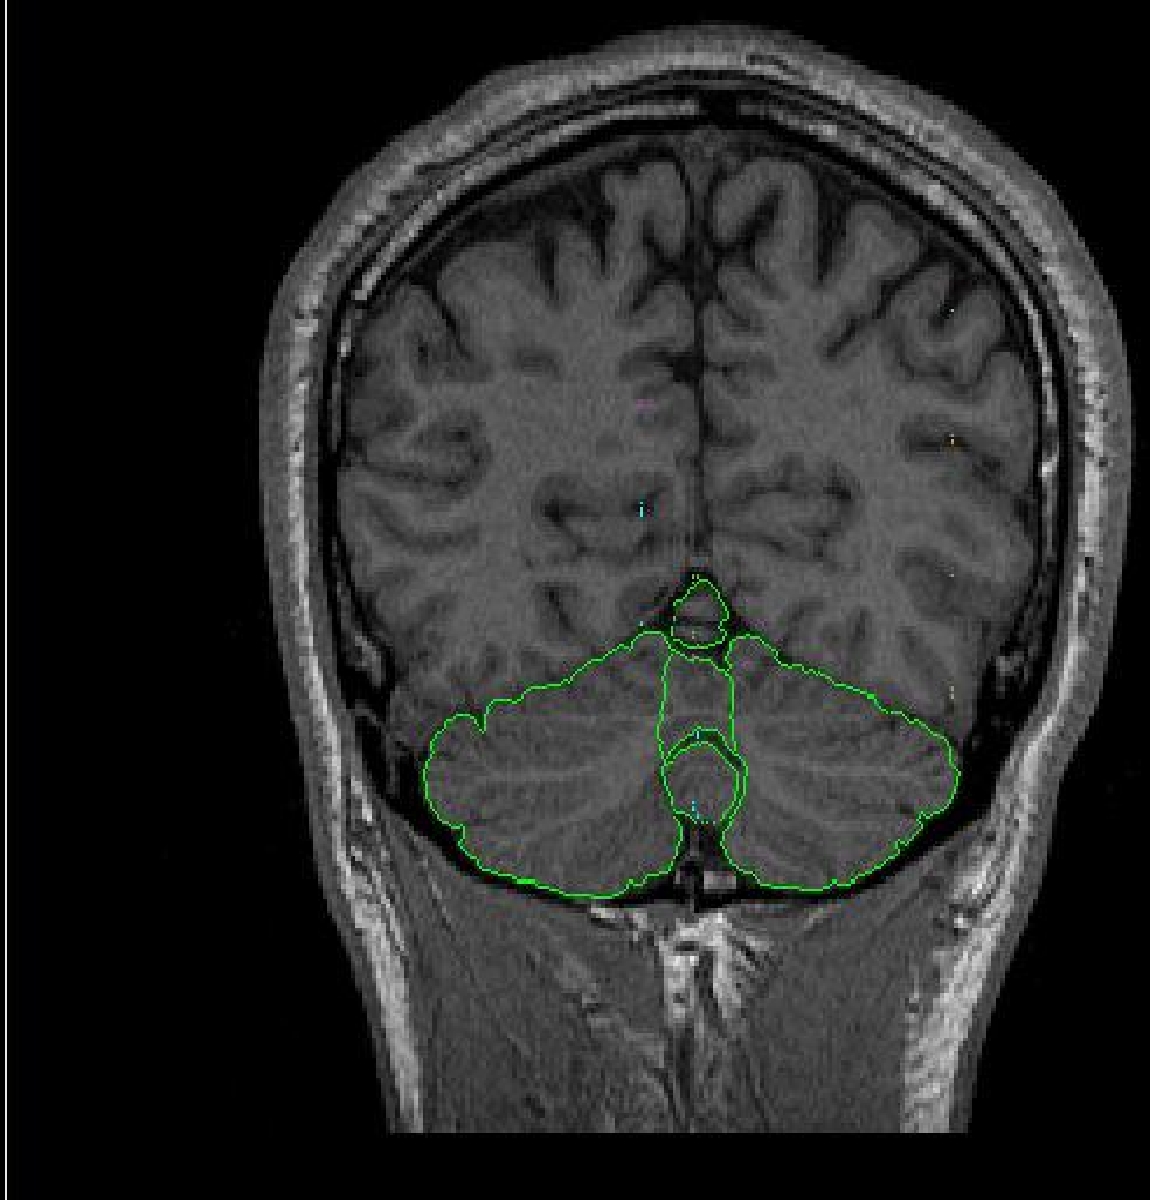

The cerebellum is located anterior to the brainstem and inferior to the cerebrum.

The cerebellum can be sectioned into the vermis and the right and left hemispheres.

Between the cerebellum and the brainstem, and between the left and right

hemispheres of the cerebellum is the 4th ventricle. Although the cerebellum

is anterior to the brainstem, the brainstem and cerebellum often show up

on the same coronal slices due to the fact that the cerebellum curves around

the brainstem. The cerebellum is surrounded by external dura, the transverse

sinus, and other non-brain tissue. Because of its location close to the brainstem

and the base of the brain, there are many nerves and blood vessels.

The cerebellum is extracted by using the intensity contour function. The correct

contour for the outline is usually the same as the outline for the cerebral

exterior. In order to see the full extent of the cerebellum it is helpful

to increase the brightness of the screen similar to the brightness used for

the cerebral exteriors. Sulci lines are in the sagittal view to determine

the vermal lobules. The cerebellum is segmented into three vermal lobules

(l-V, Vl-Vll and Vlll-X) as well as the right and left hemispheres.